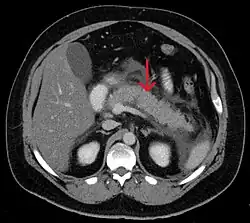

Calcified pancreatic duct stones with some free intra-abdominal fluid

A contrast-enhanced CT scan is usually performed more than 48 hours after the onset of pain to evaluate for pancreatic necrosis and extrapancreatic fluid as well as predict the severity of the disease. CT scanning earlier can be falsely reassuring.[34]